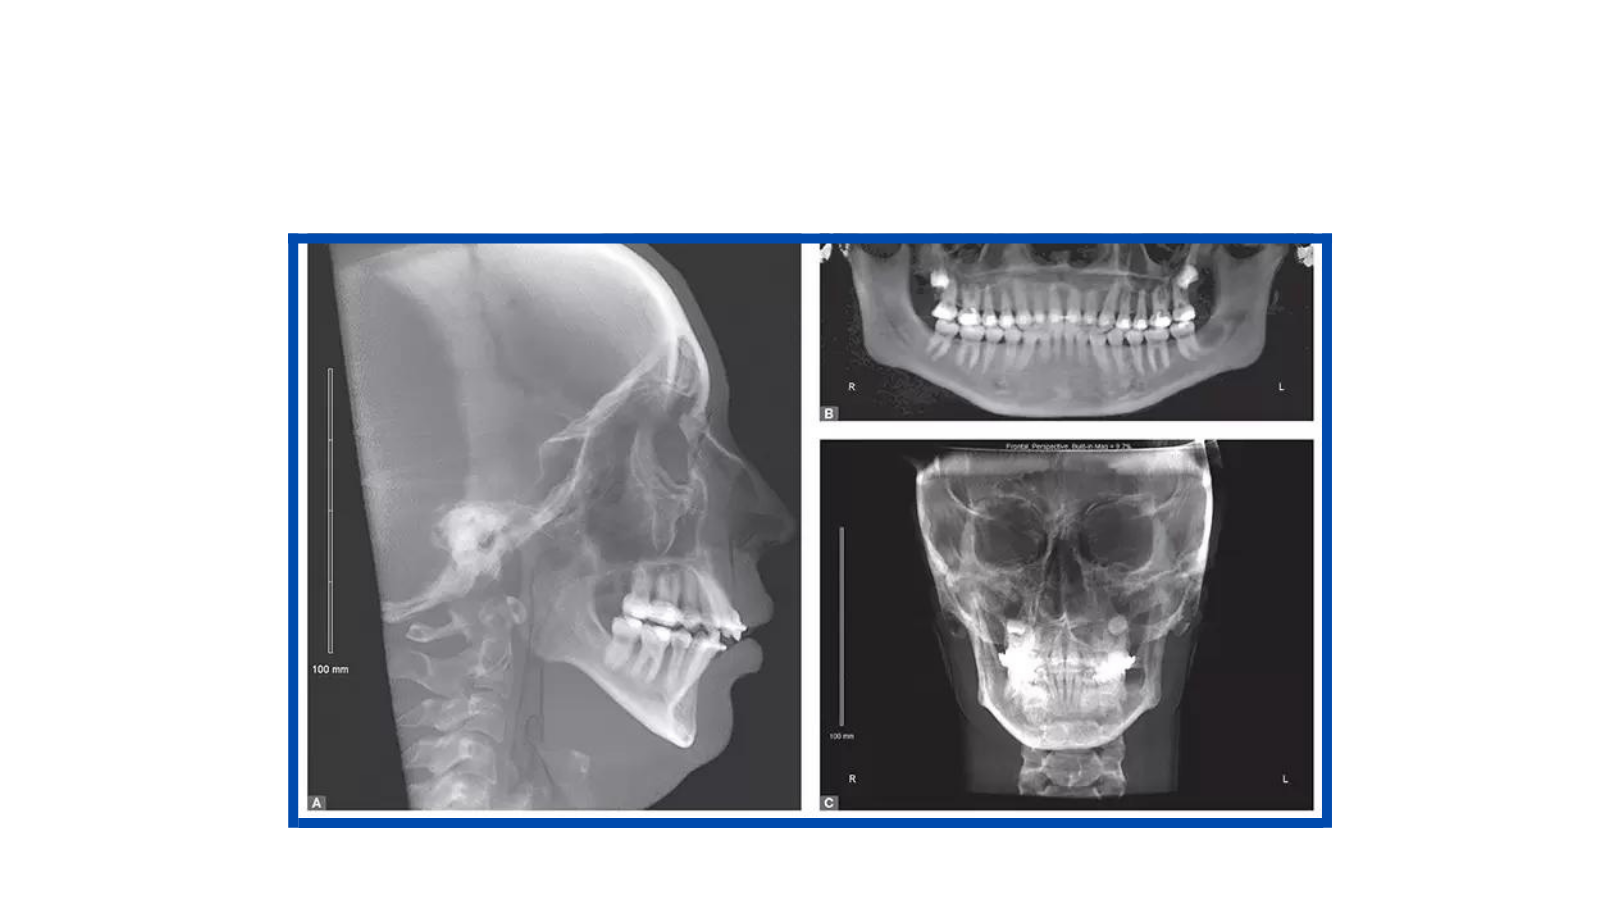

Documentações Ortodônticas

A documentação ortodôntica é um conjunto de exames composto por radiografias, fotografias intra e extra-bucais, modelos em gesso das arcadas dentárias, análises cefalométricas e de modelos computadorizados que o dentista solicita para ter uma visão abrangente e detalhada do caso de seu paciente.